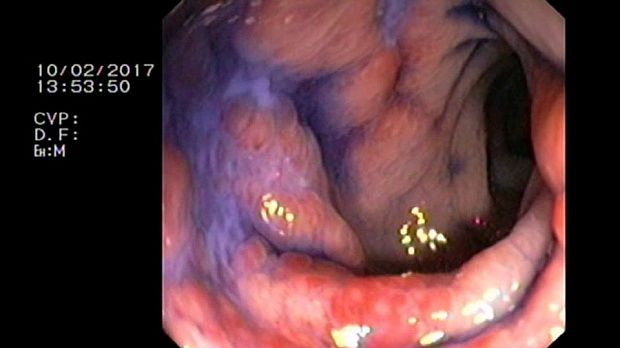

- Атлас

2 мл ( это мин сум, а мы делаем до 10 мл 3% перекись+200 мл физ раствора